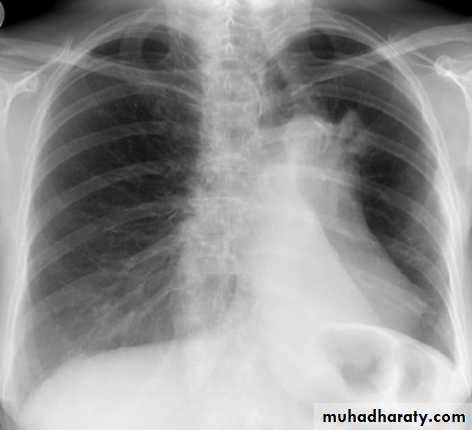

Right middle lobe collapse has distinctive features, and is usually relatively easily identified.

Radiographic features

Chest radiograph

Frontal chest XR showing opasity cause obscuration of the RT cardiac border

Lateral chest XR film the opacity is tongue like shape

versus (triangular in shape) in RT middle lobe consolidation seen in lateral chest XR film

RT lower lobe collapse

usually the medial aspect of the dome of right hemidiaphragm is lost.the right hilum is depressed

It is important to note that the right heart border, which is contacted by the right middle lobe remains well seen.

Non-specific signs indicating right sided atelectasis may also be present (although due to the small size of the right middle lobe they may well be subtle). They include:

elevation of the hemidiaphragm

crowding of the right sided ribs

shift of the mediastinum to the right